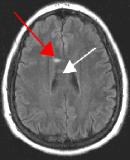

Fig. 3

Thin-section sagittal FLAIR images increase detection of small MS plaques even further, first reported by Hashemi, et al. (Ref. 1). They also have the advantage of clearly showing the corpus callosum and subependymal regions. An early sign of MS is subependymal nodularity and subcallosal striations (Ref. 1-2), not clearly visible on axial images. Fig. 3-4 in the same patient clearly show subcallosal MS plaques (arrows) along the undersurface of corpus callosum.